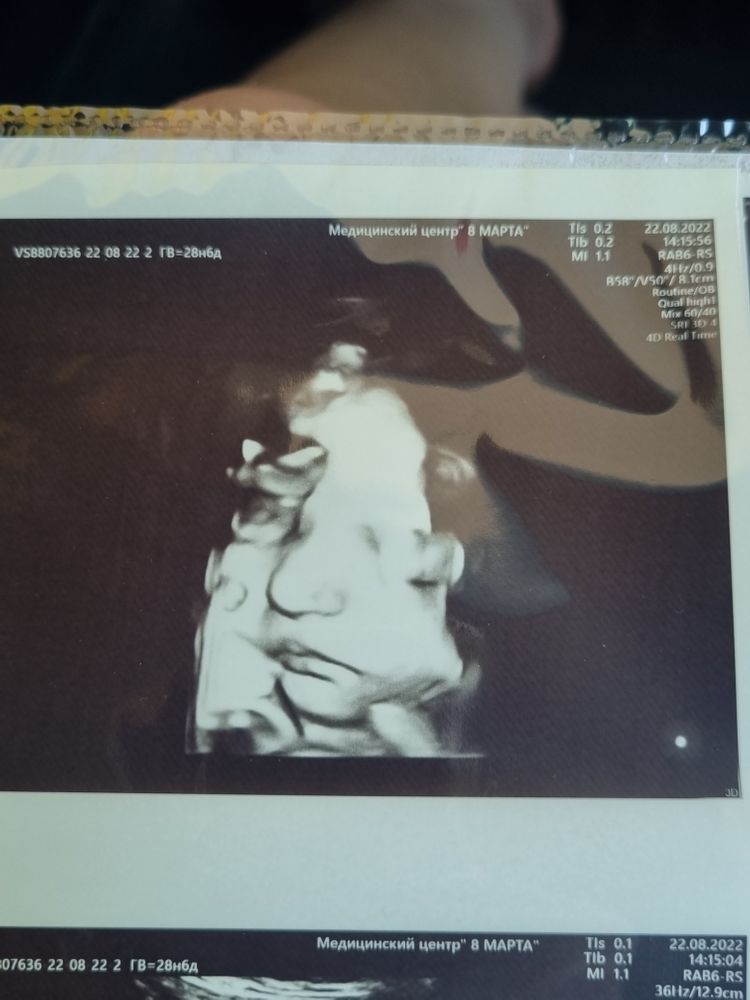

3)хочу сделать 3д узи, кто на каком сроке вообще его делал и какой срок идеален?потому что мы пришли к заключению что на плановом скрининге в 32 недели сделают

Почти 29 недель, уже очень классно видно было. Нам и на втором скриненге включали, но это не то, сейчас прям черты лица можно все рассмотреть

Почти 29 недель, уже очень классно видно было. Нам и на втором скриненге включали, но это не то, сейчас прям черты лица можно все рассмотреть